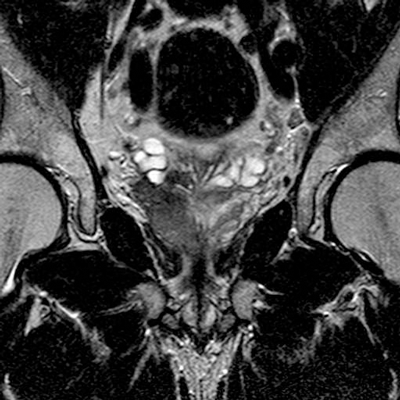

Figure 7: Axial T2 showing extensive prostate tumour invading the bladder and bilateral iliac lymph nodes.

Lymphadenopathy and distant metastases

Large FOV axial T1W images are most useful for identifying local adenopathy. Criteria similar to those used in CT staging are often applied to MR to define clinically significant nodal involvement. Enlarged, spherical lymph nodes measuring at least 1cm in short axis dimension with loss of normal internal architecture are considered significant (Figure 7). Large FOV multiplanar T2W images of the abdomen and pelvis may be acquired to look for distant nodal disease or distant organ involvement. This is used in conjunction with CT, particularly in stage III or IV disease and when considering pre-treatment lymph node sampling [7]. T1 images should be evaluated to assess for bone metastases and will be seen as low signal intensity compared with the normal high signal marrow fat.